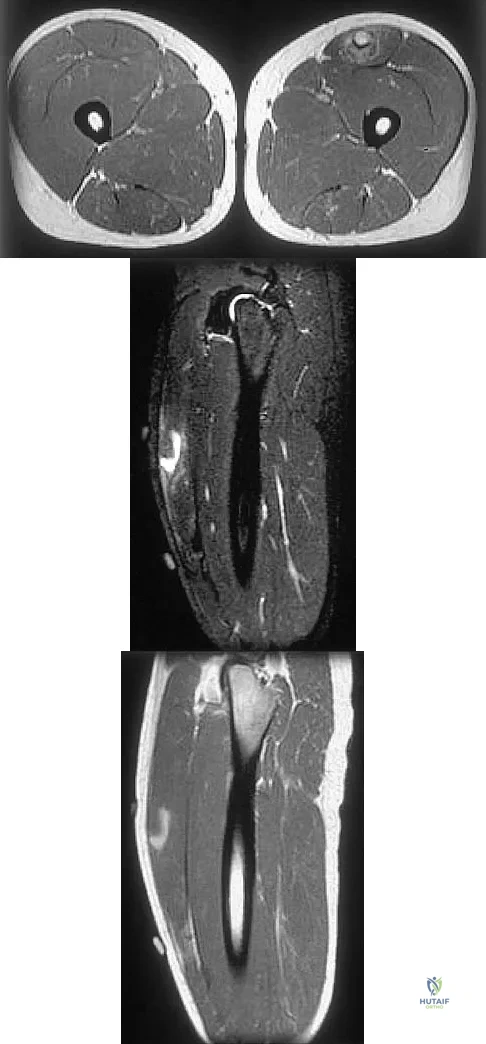

Figures 34a through 34c show an axial proton density (spin echo long TR, short TE) image, a sagittal inversion recovery (STIR) image, and a sagittal T1-weighted (short TR, short TE) image of the left thigh. What is the most likely diagnosis?